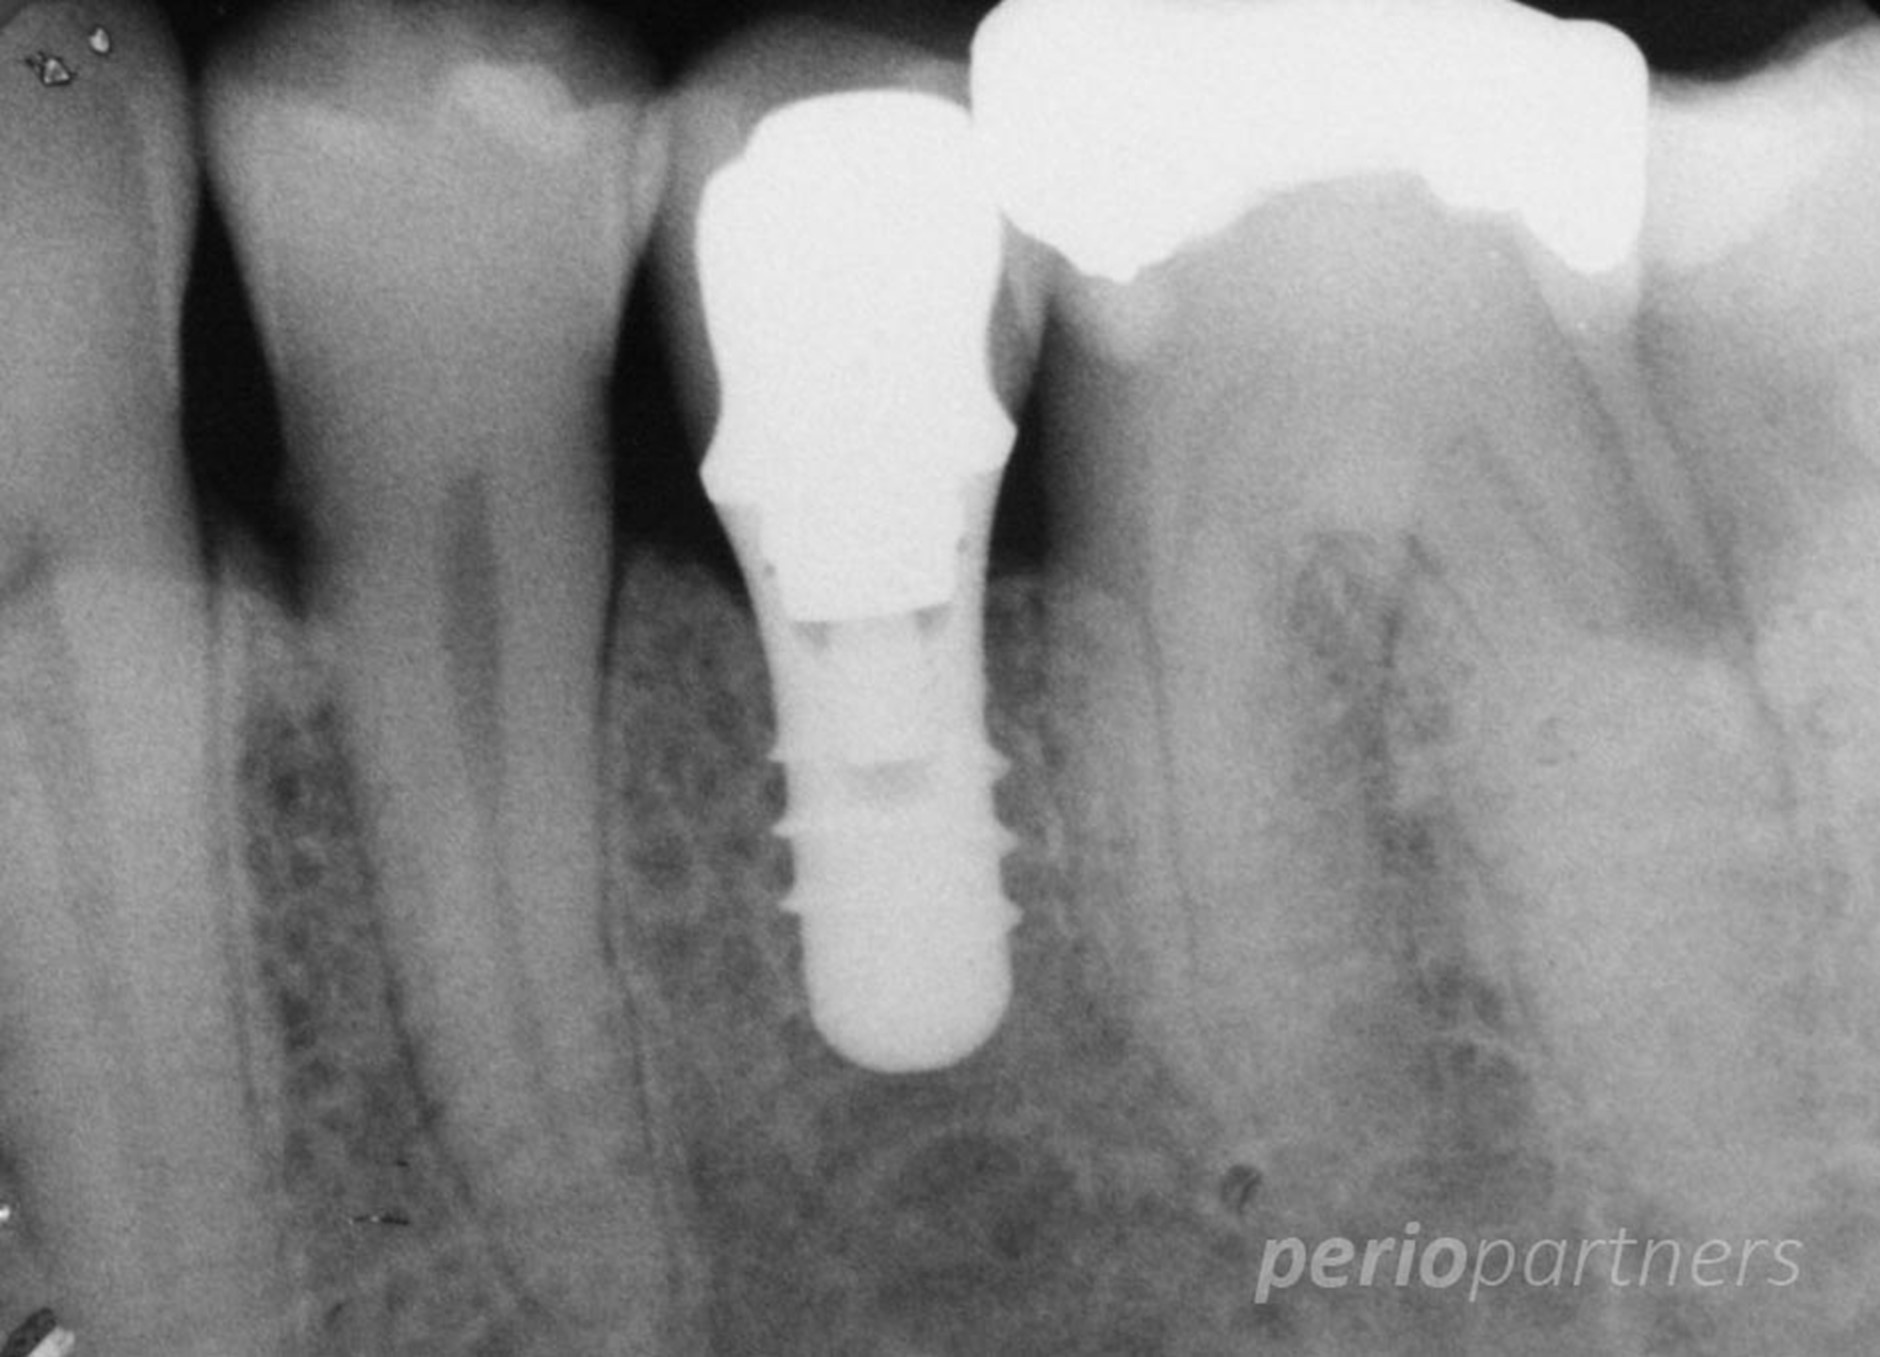

Dental implants have become the treatment of choice for the replacement of missing teeth in many situations. Dental implants can be used to support single teeth, multiple teeth (bridgework) or even full arch situations (denture or bridge). Dental implants involve the placement of an implant fixture (a medical grade titanium implant) in the jawbone, following which a tooth (crown) can be placed onto the implant. In this situation, the implant serves as the foundation of the new tooth. In most situations, the surgery for placing a single tooth implant will take less than 90 minutes. As the dental implant relies upon bone for anchorage, where the volume of bone is insufficient, bone grafting procedures may be required.

At Perio Partners, our practitioners are highly trained in the surgical placement of dental implants. We use only the most reputable implant systems and are dedicated to the follow up and long-term care of implants.

Peri-implant infections, including peri-implant mucositis and peri-implantitis, are challenging complications that periodontists manage due to the complex anatomy of implants and the often aggressive progression of disease. While early stages like mucositis may respond to nonsurgical treatments such as mechanical debridement and antimicrobial therapy, peri-implantitis frequently requires surgical intervention. Surgical approaches allow for access to thoroughly decontaminate implant surfaces, resect or regenerate affected bone, and improve long-term stability. Despite treatment, managing these infections remains difficult, and outcomes can be unpredictable, especially in advanced cases.